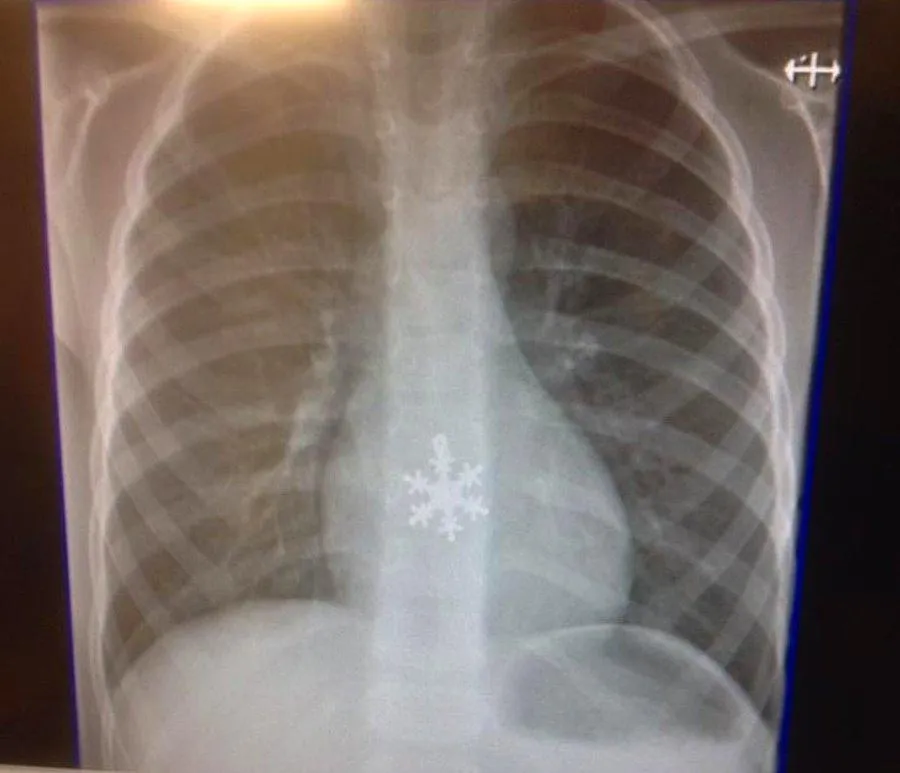

Когда во время предложения что-то пошло не так...

Фото kienthuc